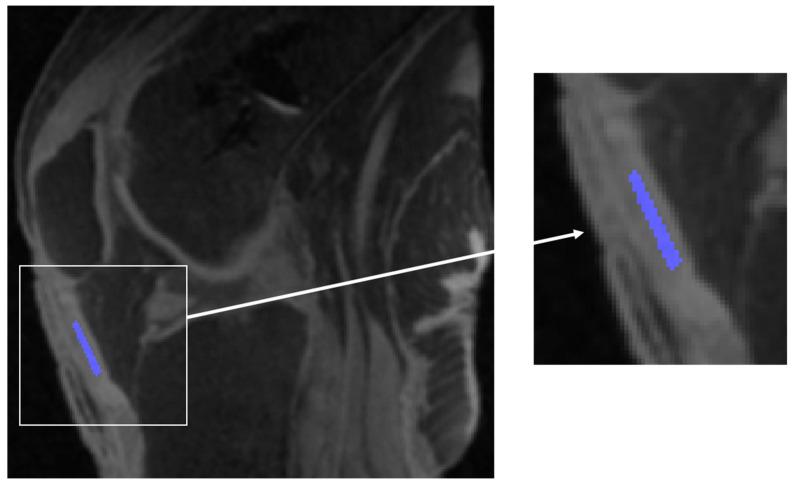

: The objective of this study was to assess the bi-exponential relaxation times and fractions of the short and long components of the human patellar tendon ex vivo using three-dimensional ultrashort echo time T1ρ (3D UTE-T1ρ) imaging. : Five cadaveric human knee specimens were scanned using a 3D UTE-T1ρ imaging sequence on a 3T MR scanner. A series of 3D UTE-T1ρ images were acquired and fitted using single-component and bi-component models. Single-component exponential fitting was performed to measure the UTE-T1ρ value of the patellar tendon. Bi-component analysis was performed to measure the short and long UTE-T1ρ values and fractions. : The single-component analysis showed a mean single-component UTE-T1ρ value of 8.4 ± 1.7 ms for the five knee patellar tendon samples. Improved fitting was achieved with bi-component analysis, which showed a mean short UTE-T1ρ value of 5.5 ± 0.8 ms with a fraction of 77.6 ± 4.8%, and a mean long UTE-T1ρ value of 27.4 ± 3.8 ms with a fraction of 22.4 ± 4.8%. : The 3D UTE-T1ρ sequence can detect the single- and bi-exponential decay in the patellar tendon. Bi-component fitting was superior to single-component fitting.

使用3T MR扫描仪上的3D UTE-T1ρ成像序列对五个尸体人膝关节标本进行扫描。采集了一系列3D UTE-T1ρ图像,并使用单成分和双成分模型进行拟合。进行单成分指数拟合以测量髌腱的UTE-T1ρ值。进行双成分分析以测量短和长UTE-T1ρ值及分数。

单成分分析显示,五个膝关节髌腱样本的平均单成分UTE-T1ρ值为8.4±1.7毫秒。双成分分析实现了更好的拟合,其显示平均短UTE-T1ρ值为5.5±0.8毫秒,分数为77.6±4.8%,平均长UTE-T1ρ值为27.4±3.8毫秒,分数为22.4±4.8%。